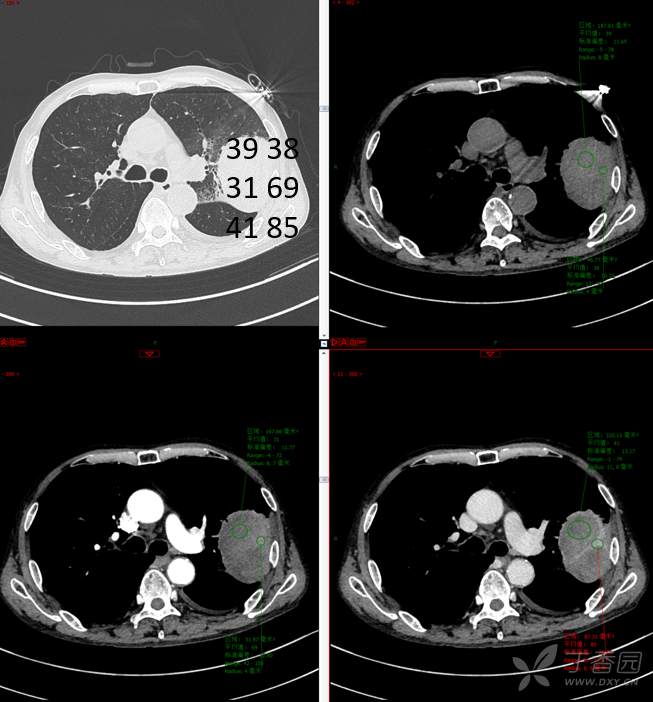

现病史:患者自诉5月前无明显原因及诱因出现纳差、乏力,伴进食后腹胀,无腹痛、腹泻、发热、盗汗、恶心、胸闷,未行特殊处理。1月前无明显原因诱因出现咳嗽,呈阵发性,咳白痰,痰中带鲜红色血丝,10余口/日,无血块,仍伴纳差、乏力、进食后腹胀,无恶心、呕吐、呕血,无头晕、心慌、喘憋、胸闷。在家未行特殊治疗,来我院就诊,2022.8.18行胸部(肺)CT平扫:左上肺占位并左侧肋骨骨质破坏,考虑间叶源性恶性肿瘤。门诊以“肺肿物”收入我科。患者自发病以来,神志清,精神可,饮食差,睡眠可,二便正常,近3月减轻5Kg。